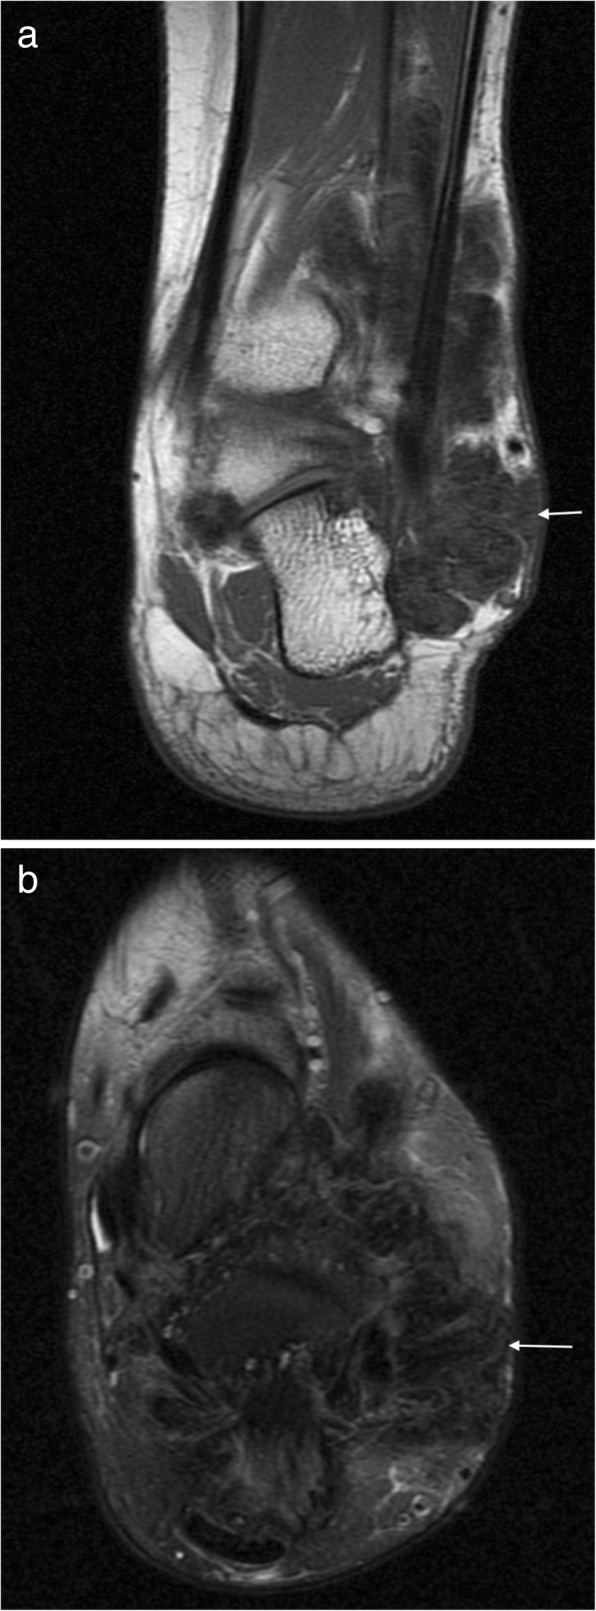

Fig. 1.

Plantar fibroma. a Sagittal T2 fat suppressed (T2FS) and (b) coronal T1-weighted image of the foot demonstrating a heterogeneous mass centred on the plantar fascia, distinct from the underlying musculature. The characteristic low signal linear bands are shown (arrows)

Ultrasound alone may be sufficient for diagnosis in plantar fibromatosis. It appears as a fusiform hypoechoic or heterogeneous mass arising from the plantar fascia [16, 19]. Similarly, on MRI, it is seen as a fusiform mass arising from the plantar fascia, more often medial than lateral [16, 17]. It is usually heterogeneous in signal intensity, hypointense to skeletal muscle on T1-weighted (T1W) imaging and iso- to hyperintense to skeletal muscle on T2-weighted (T2W) imaging (Fig. 1) [14–21]. Early lesions are more cellular and tend to be more hyperintense on T2W imaging, whereas more mature lesions tend to be more fibrotic with low signal on T2W [15]. The deep margin is often not well demarcated from the underlying muscle, but the superficial margin is usually clearly defined. It demonstrates variable enhancement on post contrast imaging, which is not generally required for the diagnosis [14, 17].